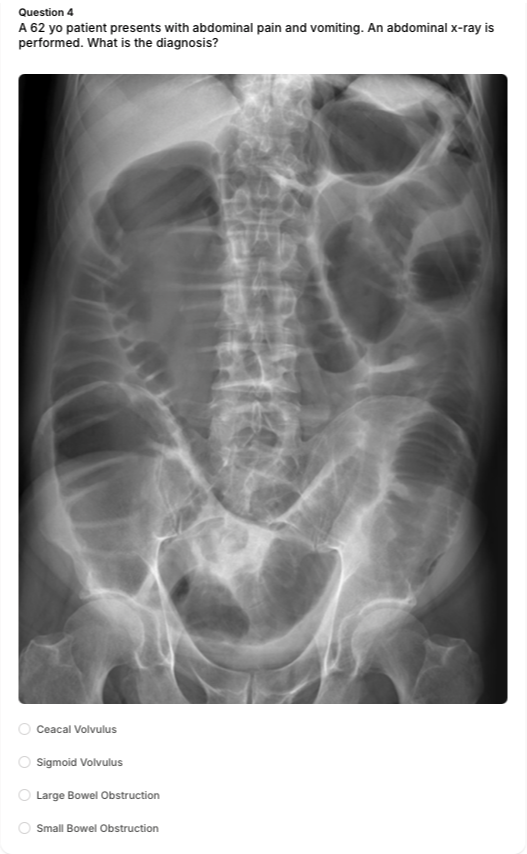

• Imaging